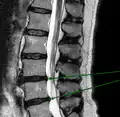

L'imagerie par résonance magnétique peut montrer la hernie, le canal vertébral, les nerfs, les tissus environnants. Les tissus mous sont les mieux analysés par cet examen qui est le plus performant pour le diagnostic de hernie discale. Les images pondérées en T2 montrent clairement la hernie.

IRM lombaire sagittale montrant des protrusions discales. IRM lombaire sagittale montrant des protrusions discales.